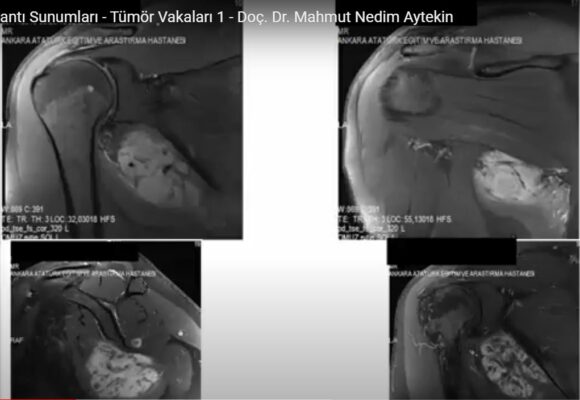

Kanserin Kemiğe Sıçraması, Sonucu Kanserli Kemik Hücreleri Tedavi Edilebilir Mi?

Bilimsel Toplantı Sunumları – Ortopedik Onkoloji’de Pet(BT ve MR) Yeri ve Sınırları